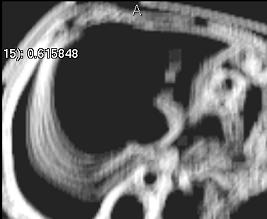

Average (simple)

../../../Modules/ML/MLFilter2/mhelp/Images/TextureFilterImages/average.jpg